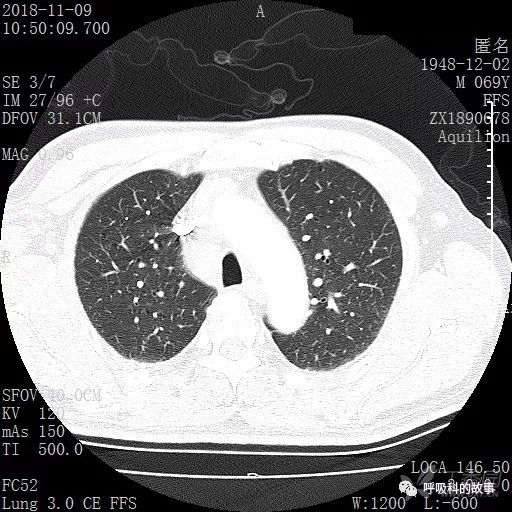

肺窗CT